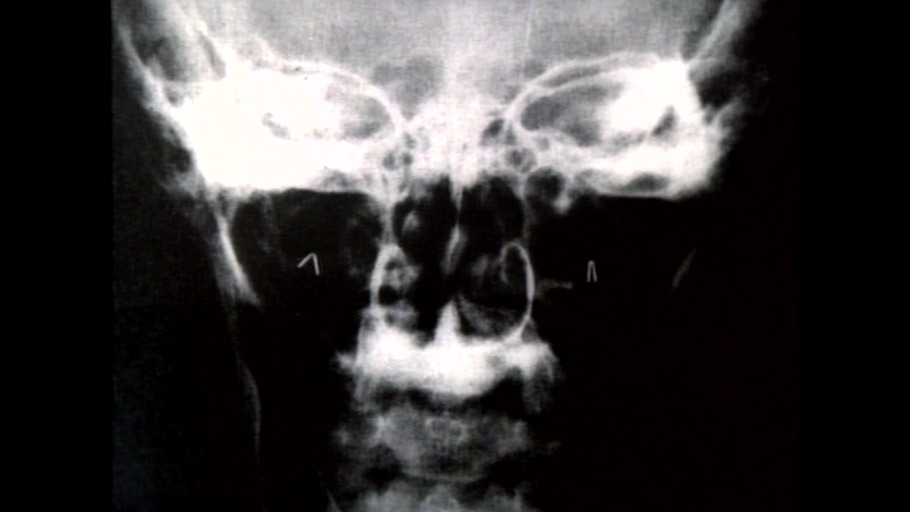

Mit neuen Methoden untersuchen die Hirnforscher die Eigendynamik unseres Gehirns. Sie messen außen an der Kopfhaut, weiter innen an der Hirnhaut und auch im Hirn selbst.

Gehirne variieren individuell so, wie sich Gesichter oder Fingerabdrücke unterscheiden. Der Arzt und Gehirnforscher Detlev B.. Linke berichtet zum Stichwort: Geografie des Gehirns.

In dem neuesten Film von Robert Bramkamp "Die Eroberung der Mitte" geht es um wirkliche Tumore, Falschdiagnosen und allgemeine Hysterie